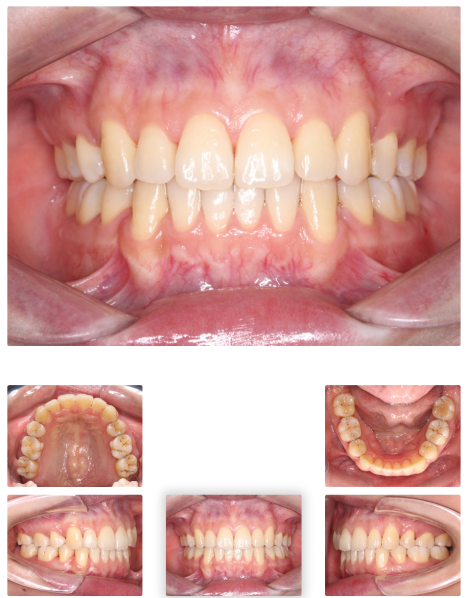

발치 + 인비절라인 돌출입 개선 사례

바로 사례부터 보여드릴게요.

"입이 나와 보여요"라며 찾아주신 여성 환자분이셨는데요.

치료 전 X-ray 측면 모습으로도 치아가 앞으로 기울어져 있고,

입이 튀어나온 모습을 확인할 수 있습니다.

돌출입수술은 무섭고, 회복도 걱정돼

비수술적인 방법을 찾다가 인비절라인을 선택하게 되셨는데요.

상악, 하악 각각 첫 번째 소구치를 발치했고,

인비절라인을 통해 치아를 뒤로 이동시키며 돌출을 점진적으로 개선했습니다.

뻐드러져 있던 치아 배열 모습이 정상적으로 돌아온 걸 확인하실 수 있을 겁니다.

총 치료 기간은 약 20개월이 걸렸는데요.

치료 전후 X-ray 사진을 비교해 보면,

기울어졌던 앞니가 정상 각도로 줄어들었고 자연스레 돌출입도 개선된 걸 볼 수 있지요.

입술 라인도 부드럽고 자연스럽게 닫히며,

잇몸 노출도 줄어들어 웃는 인상까지 부드러워졌는데요.

교정 끝난 뒤엔 라미네이트도 추가해 앞니 라인이나 색상까지 정리해 드렸습니다.